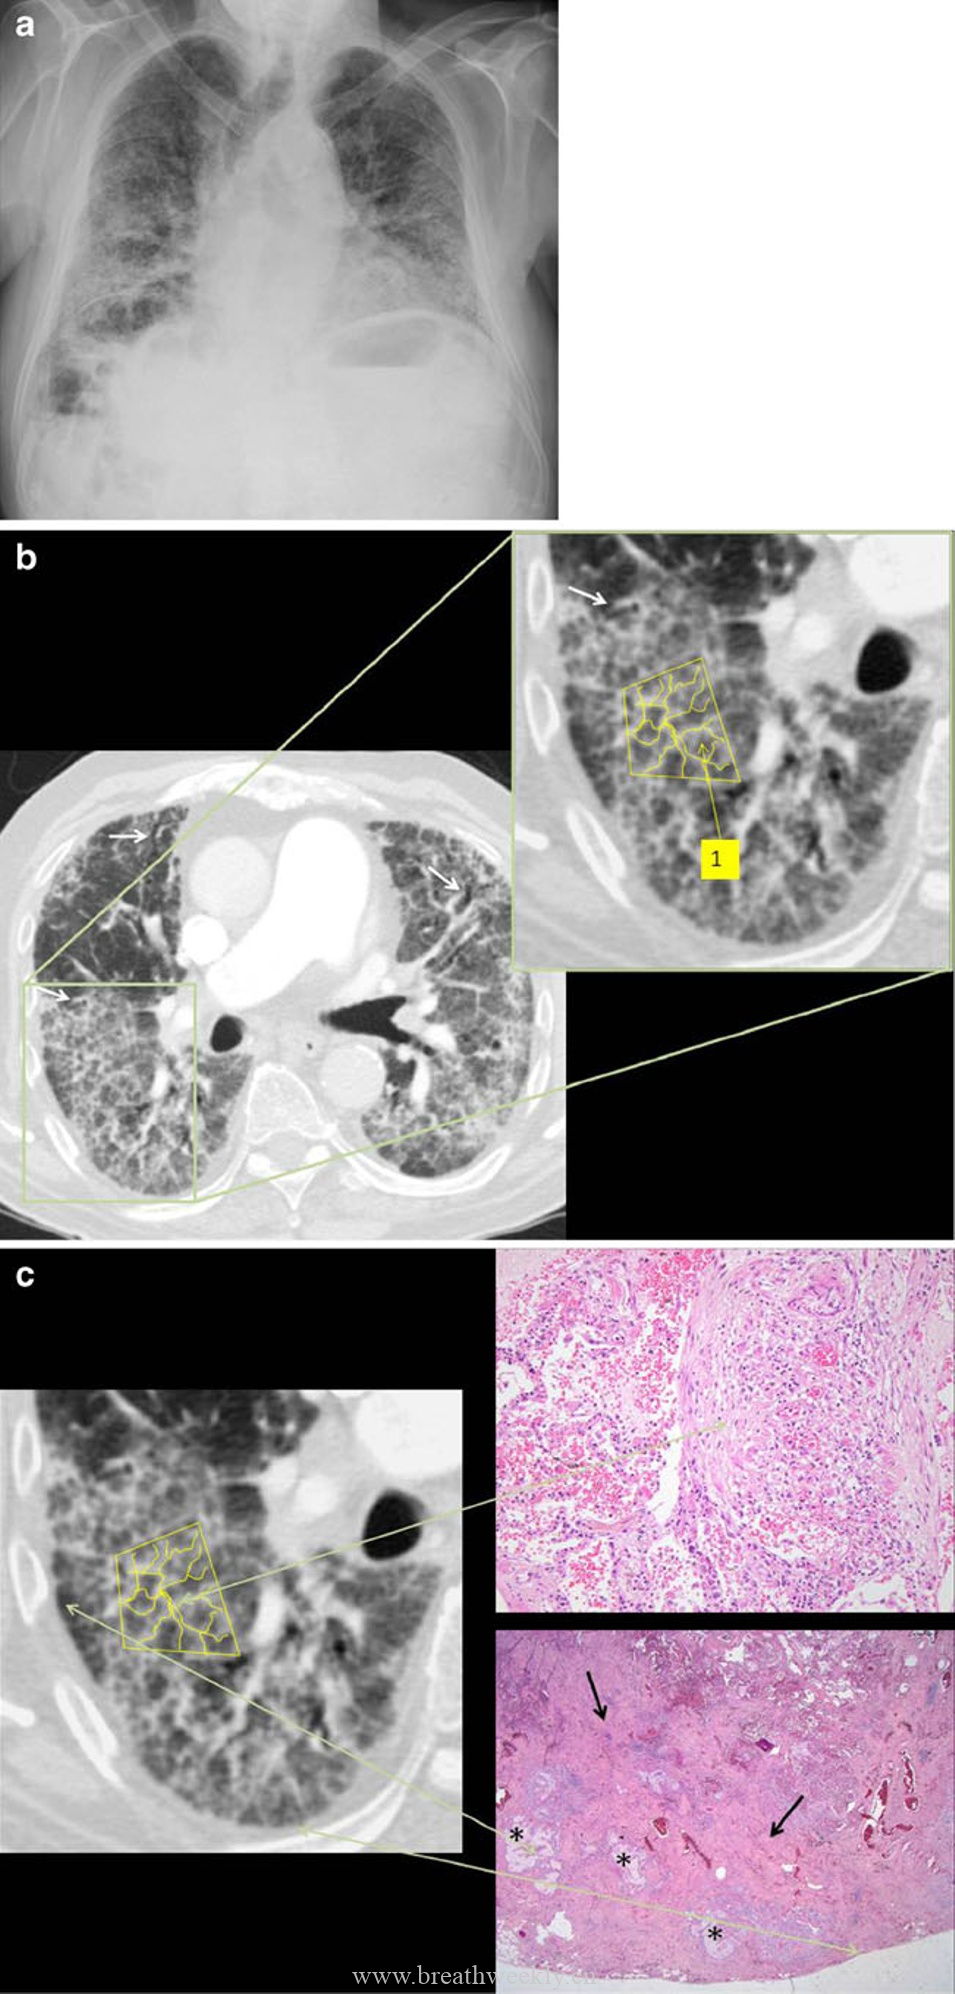

5. 耶氏肺孢子菌肺炎(PCP)

典型表现:免疫抑制患者,双肺门周围分布,可伴囊肿。